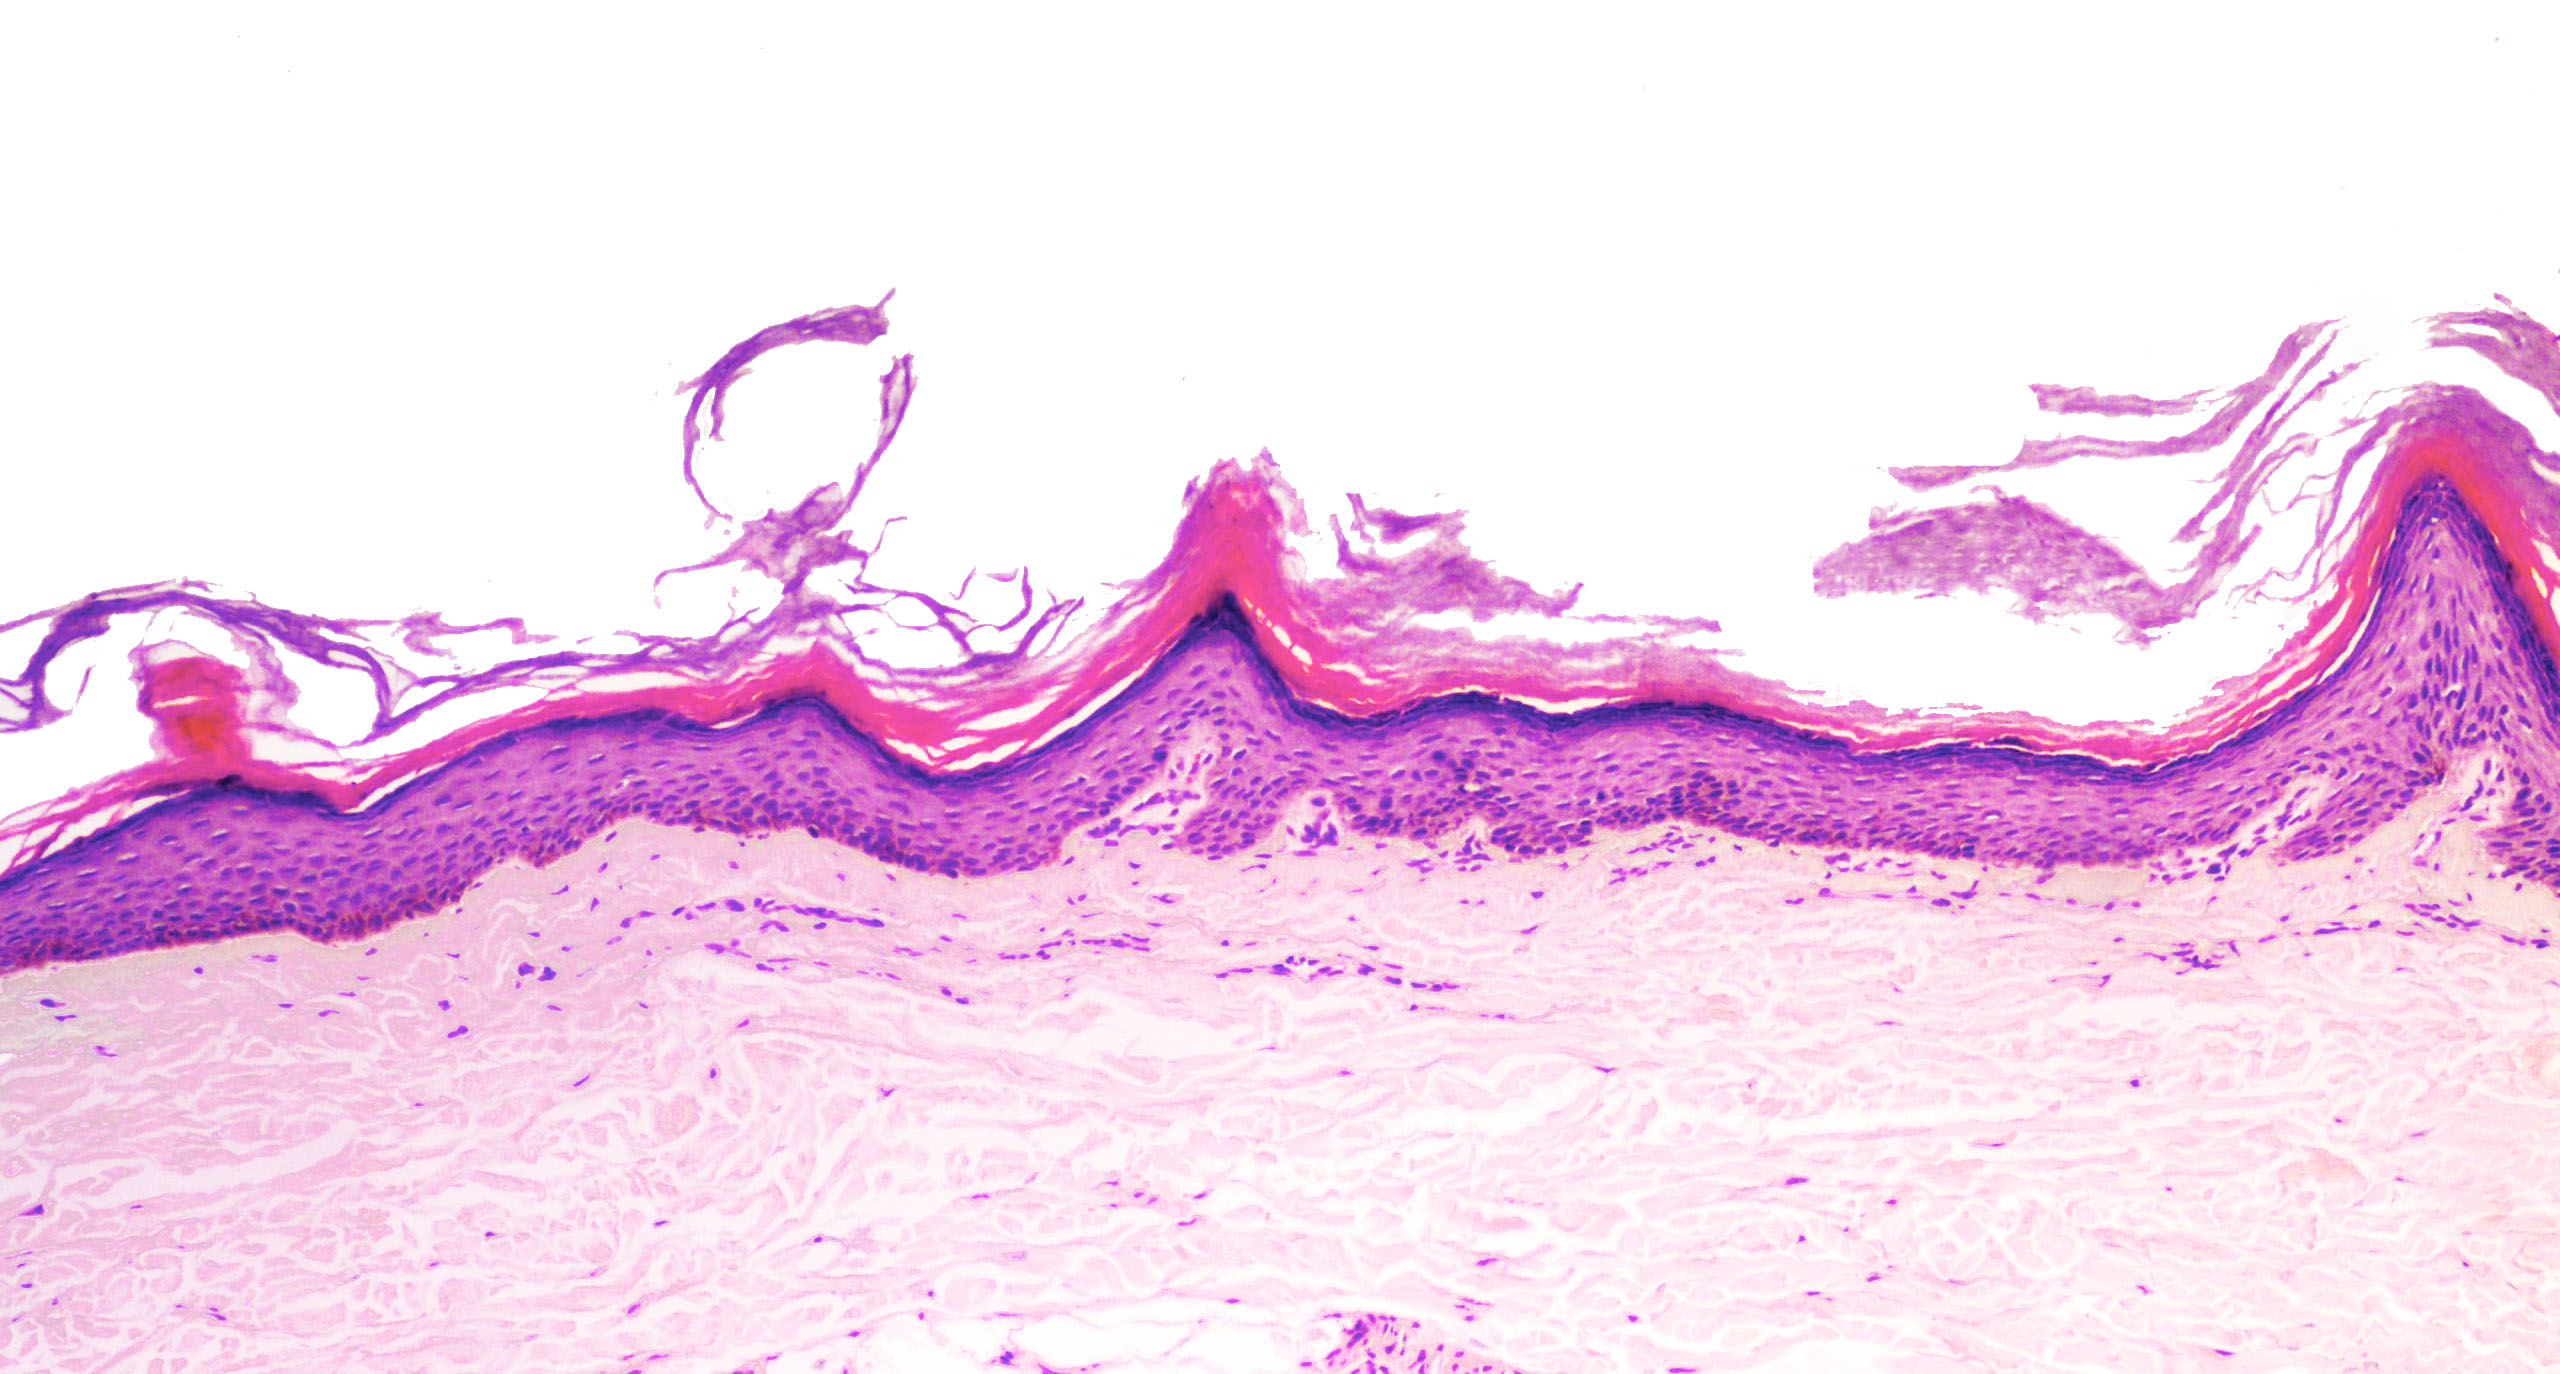

Microscopic (histologic) description

- Parakeratosis

- Variable epidermal thickness

- Flat topped acral papules demonstrate orthokeratosis (may be church spire type), hypergranulosis and papillomatous epidermal hyperplasia; acantholytic dyskeratosis is often subtle or absent

Microscopic (histologic) images

- Acrokeratosis verruciformis of Hopf:

- Church spire hyperkeratosis, hypergranulosis and papillomatous epidermal hyperplasia

- Lesions may be identical to flat topped acral papules of Darier disease (J Dermatol 2016;43:275, J Invest Dermatol 2003;120:229)

- No acantholytic dyskeratosis seen